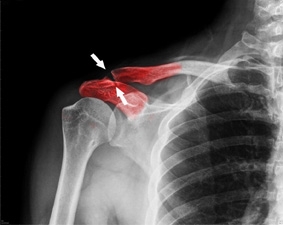

- Điều trị hiệu quả các bệnh xương khớp tại Trung tâm Y tế khu vực Thốt Nốt